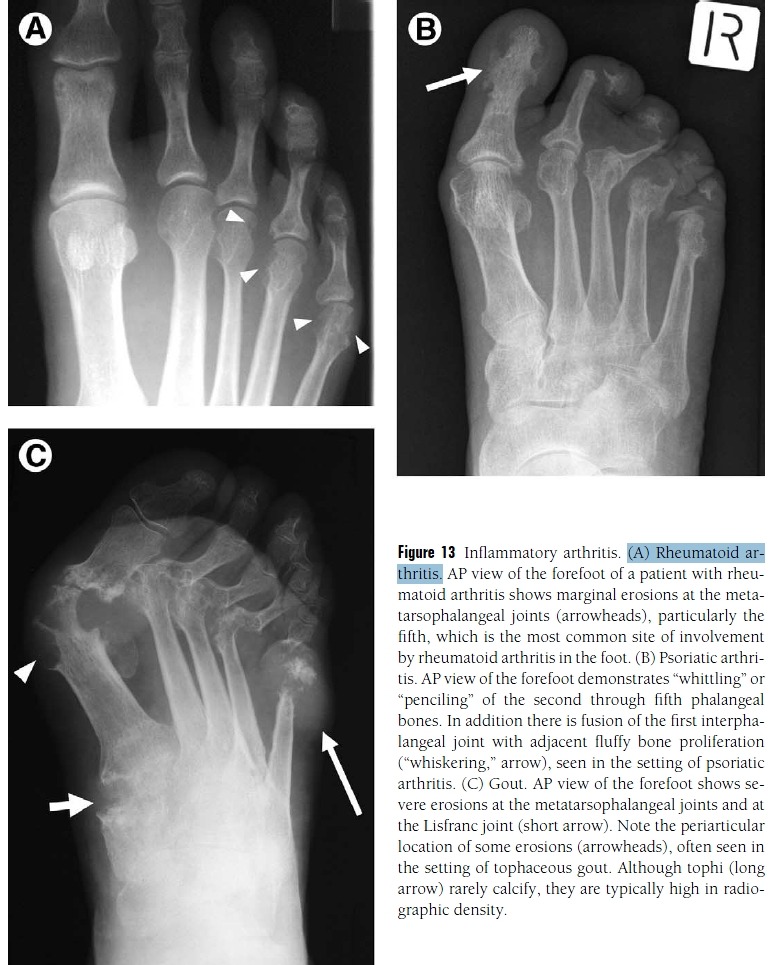

Figure 12 Osteoarthritis.

(A) Osteoarthritis of the first metatarsophalangeal joint is common; a prominent dorsal osteophyte may form

(arrow) called a “hallux rigidus spur.” Like impingement syndromes at the ankle, this condition is associated with pain and limited range of motion at the joint.

(B) Ankle joint osteoarthritis with anterior impingement. Lateral view of the ankle shows narrowing of the

ankle joint (arrowheads) and subchondral sclerosis representing osteoarthritis. Anterior spurs (arrows) can cause pain and limited dorsiflexion, called “anterior impingement.”